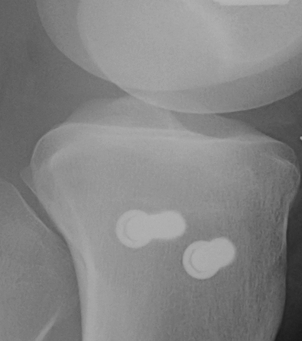

1. Medial and Lateral Plating

Technique

- depends on which of the three columns affected

- anterolateral approach for lateral column

- posteromedial appraoch for medial / posterior column